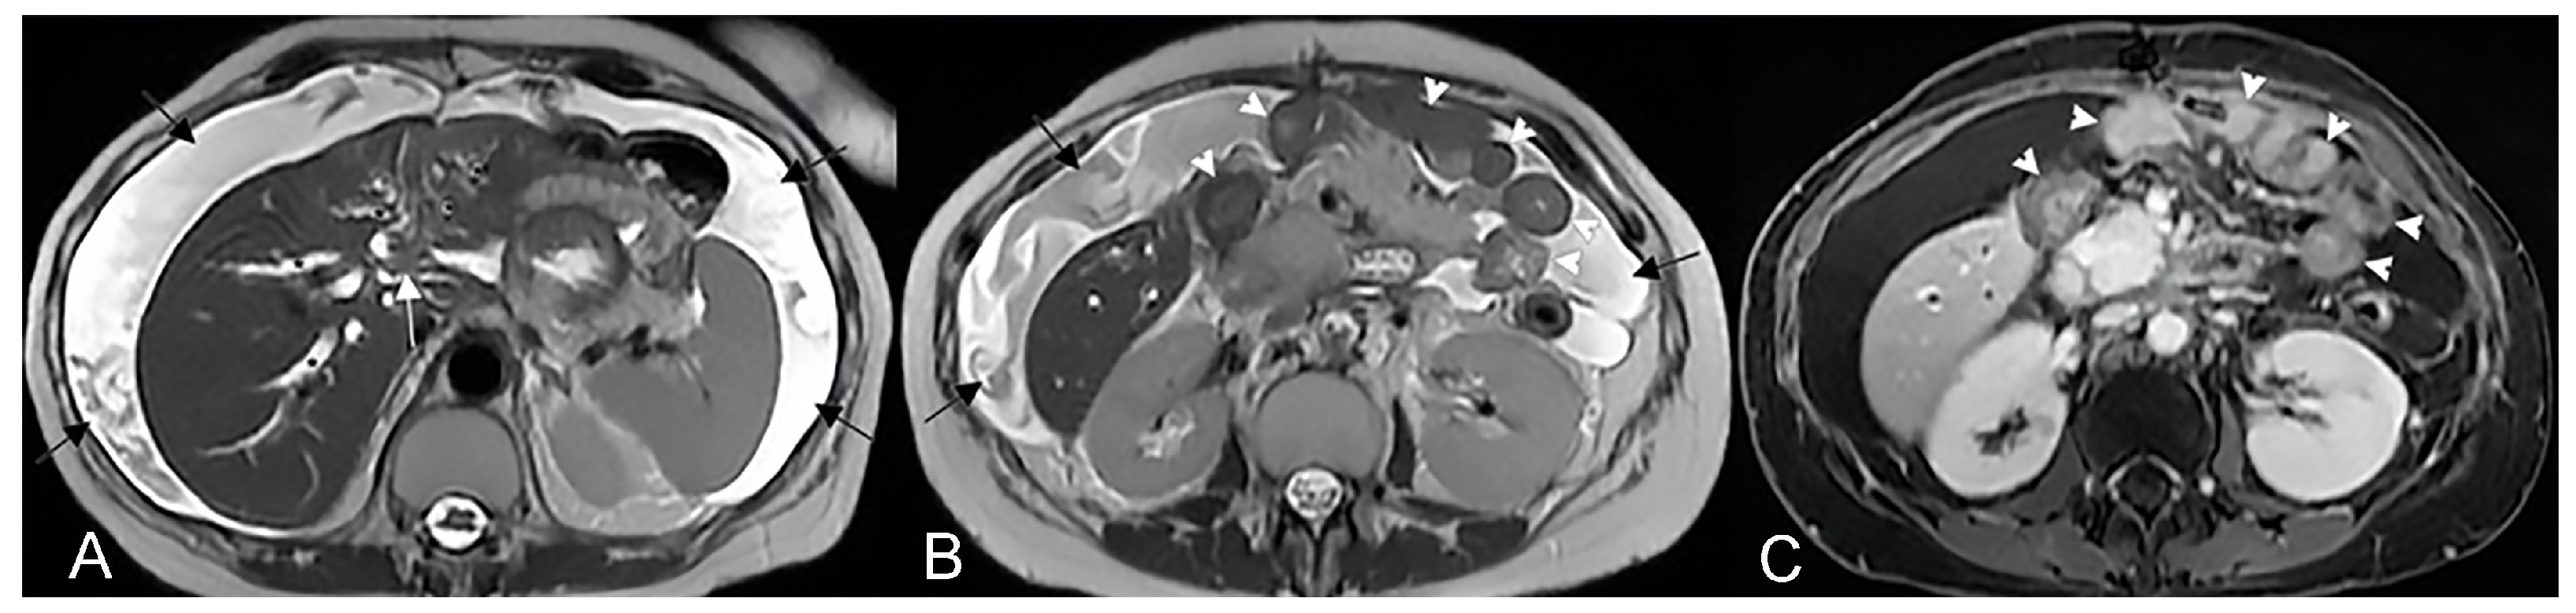

Extension, degree of wall thickening, and type of wall enhancement depend on the cause of ischemia (occlusion of the artery, occlusion of a vein or hypoperfusion), the degree of ischemia (transient or durable), and the coexistence of infection or hemorrhage. On MRI, bowel wall thickening is usually present, even if this sign is not observed in arterial acute occlusion. Acute ischemia can simulate different bowel conditions, and the pattern of wall thickening could be localized or diffuse, focal, or segmental, superficial or transmural. In the early stages of bowel ischemia, a stratified contrast enhancement can be observed, showing mucosal hyperemia or hypoperfusion and submucosal edema (Figure 25). Other findings such as occlusion of the mesenteric artery or vein, mesenteric venous engorgement, mesenteric edema, bowel distension, and ascites can be associate [50].

Figure 25.

A case of small bowel ischemia in a 61-year-old male patient. (A) Coronal T2-weighted and (B,C) coronal T1-weighted after gadolinium injection images show diffuse thickening of small bowel loops (white arrows) with stratified contrast enhancement due to thrombosis of superior mesenteric vein (black arrow in (C)). Multiple collateral veins (arrowheads in (B)) and free abdominal fluid are also observed.